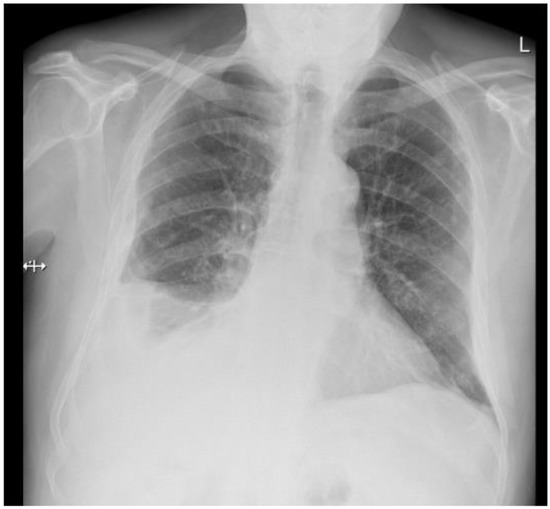

A 77-year-old man presented with several weeks of exertional dyspnea and intermittent dry cough. His past medical history was notable for ankylosing spondylitis, chronic gastritis, a left salivary gland tumor resected 11 years prior (pathologic details unknown), and a cholecystectomy. He had a significant smoking history (20 pack-years) but quit 32 years earlier. An initial chest radiograph, obtained to evaluate possible heart failure, revealed a large right-sided pleural effusion. Figure 1 A contrast-enhanced computed tomography (CT) of the chest further delineated multiple pleural nodules (up to 17 mm) and diffuse, bilateral small pulmonary nodules. Figure 2 and Figure 3 Two thoracenteses drained ~3800 mL of hemorrhagic pleural fluid in total. Fluid cytology was negative for malignancy, and no cell block preparation was performed. Further evaluation with bronchoscopy and bronchoalveolar lavage was unremarkable for infection or malignant cells.

Figure 1. Chest X-ray—right pleural effusion, thickening of the pleura on the right side, bilateral small nodules.